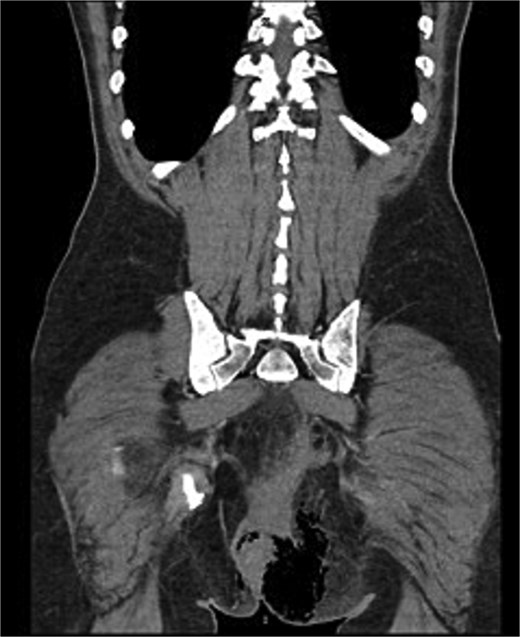

We present the case of a 47-year-old male with no prior medical history who arrived at the Emergency Department with a rapidly evolving perianal abscess (Fig. 1). Within hours, he developed Fournier’s gangrene secondary to an undiagnosed rectal neoplasm (Fig. 2).